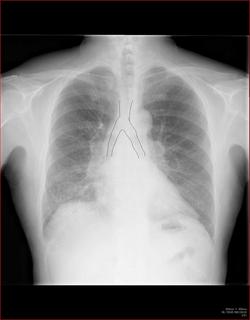

Aシルエット・サインを使う

陰影があったときに、果たしてその陰影はどこにあるのか。

上、中、下肺野のどこにあるかとともに、シルエット・サインをうまく使うことでどのセグメント(

1〜10に分かれている、例のやつ)を絞り込むことができます。